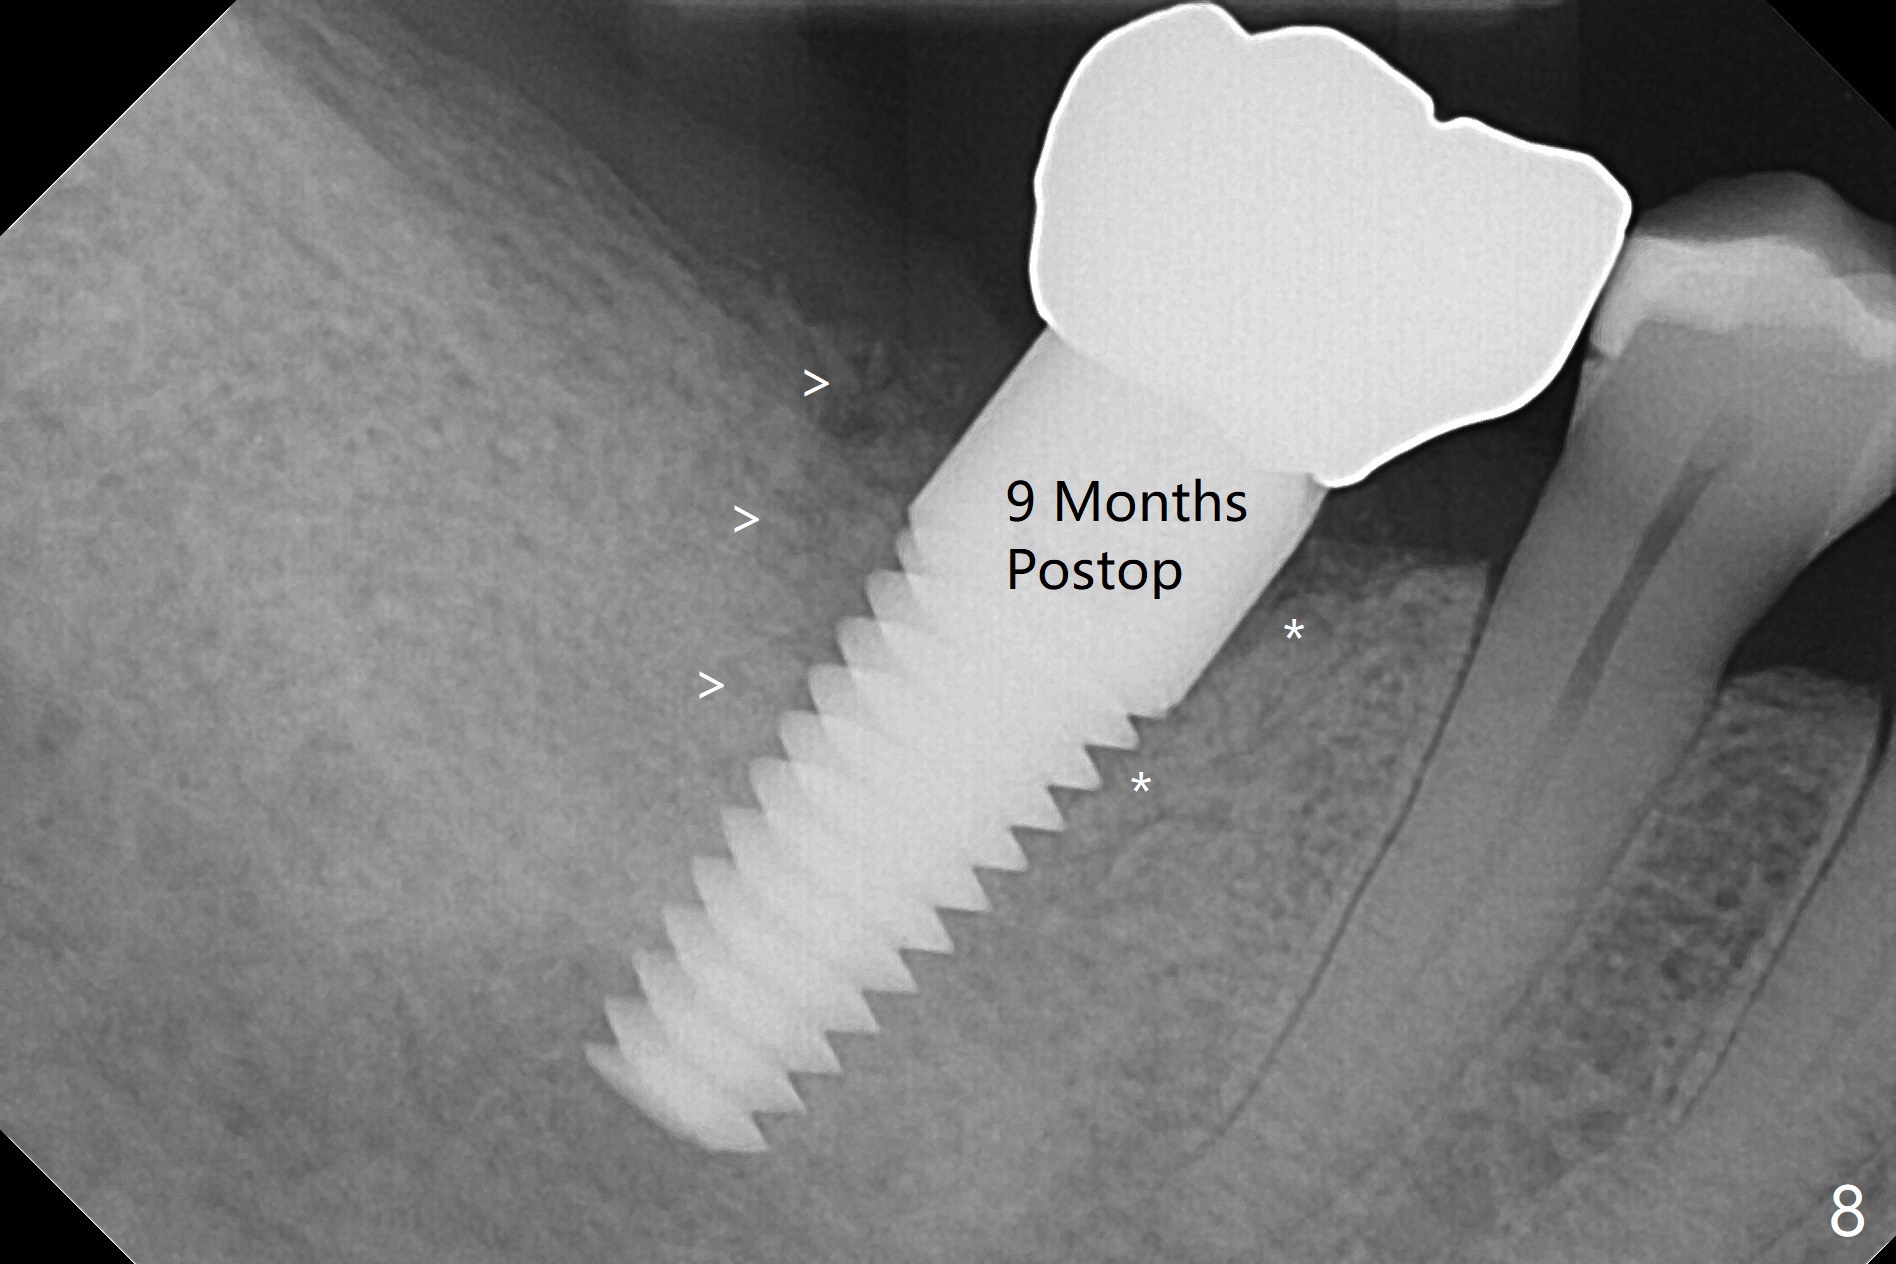

After extraction of the tooth #30 and curettage, the septum becomes so thin that the most coronal portion has to be removed with Rongeur and surgical fissure bur (bone height reduction). Initial osteotomy depth is ~ 4 mm from the flattened septum (Fig.1 (yellow dashed line: apical end of the osteotomy)). Following sequential osteotomy (with intact osteotomy wall), a 6x17 mm tap is placed with apparent clearance from the Inferior Alveolar Canal (Fig.2). When the same size implant is placed with 60 Ncm (Fig.3), the nervous patient feels that the implant is too long (causing pain). CT (Fig.4) and panoramic X-ray (Fig.5) show limited clearance (1.4 mm), but compression of the canal due to high torque could not be ruled out. Since limited amount of the native bone (4.1 mm) for primary stability, the implant is not backed up immediately. Vanilla graft is placed after fabrication of an immediate provisional (Fig.6 *). In brief, immediate implant should be avoided when the septum is thin or the native bone is less than 5 mm (3 mm for primary stability; 2 mm for clearance). In fact the implant has to be untorqued 4-5 times of turn to relieve pain nearly 1 month postop. The patient returns for impression 5 months postop (4 months post implant back up, Fig.7). When the abutment is changed to 5x5 mm and prepared, she reports earache (residual nerve damage?). The patient has had the similar complaint 9 months postop; it appears that there is radiolucency distally (Fig.8 >, as compared to radiopaque mesially (*)). The distal gingiva is tender. With a remade permanent crown, oral hygiene instruction is provided. If necessary, CBCT is taken with possible bone graft.